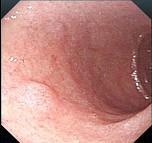

问题 男,70岁,剑突下疼痛伴进行性咽下困难1个月,消瘦、乏力明显,粪隐血持续阳性,内镜及影像检查如下图,诊断为 ( )

选项 A.胃黄斑瘤 B.贲门息肉 C.胃溃疡 D.贲门癌 E.胃癌

答案 E